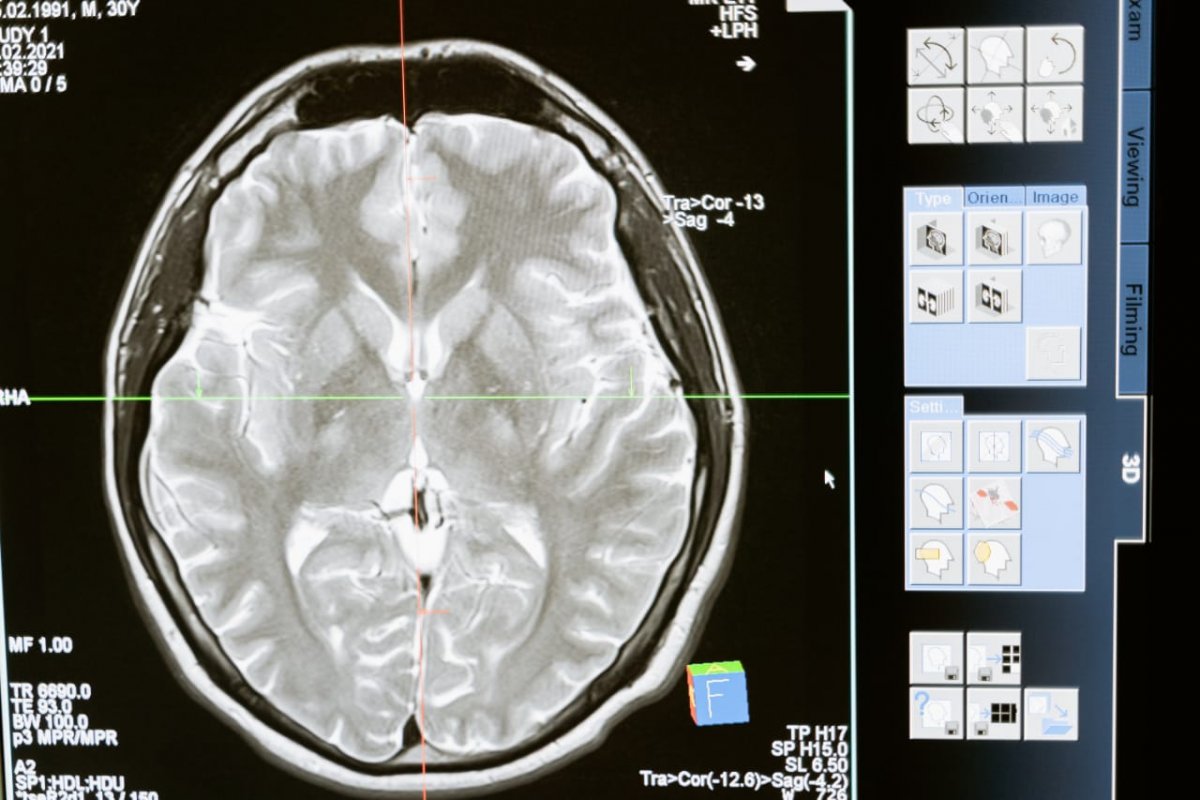

Cientistas descobriram que a Covid-19 pode causas alterações no cérebro. O estudo publicado na revista científica Nature mostra que há significativas diferenças em exames de ressonância magnética realizados em pacientes antes e depois da infecção.

Mesmo em casos de infecção leve, a investigação apontou que o o tamanho geral do cérebro havia encolhido um pouco, com menos massa cinzenta nas partes relacionadas ao olfato e à memória.

Os pesquisadores realizaram novamente os exames em 401 voluntários, cerca de quatro a cinco meses após se infectarem com a Covid-19 (96% deles tiveram sintomas leves); e em outros 384 participantes que não foram infectados pelo coronavírus.

- O tamanho geral do cérebro em participantes infectados havia encolhido entre 0,2 e 2%;

- Houve perdas de massa cinzenta nas áreas olfativas e regiões ligadas à memória;